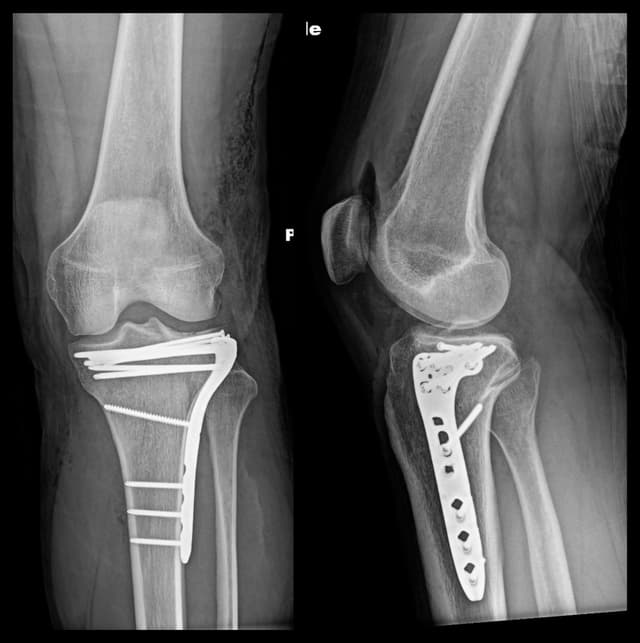

Imaging

Post-op